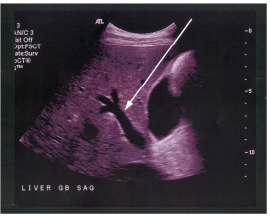

66 附圖中箭號所指的結構最可能為:

(A)主肝裂(main lobar fissure) (B)肝鐮韌帶(falciform ligament)(C)肝圓韌帶(round ligament) (D)左門靜脈